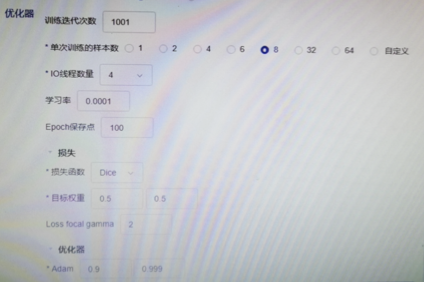

深度学习训练:相信大家一定关心它的训练模式🤭🤭。他提供二维三维的分割,ROI的分类(无法对整张图进行分类)。来看一个案例,医生如何不写 代码就完成了深度学习训练

数据准备好后,深度学习配置就只有上图两张参数,只需要勾选你要的配置即可开始训练。当然,你看不到的参数肯定就是不可调的,比如你看不到gpu的使用情况,你也不知道提供多大的算力。提供的分割模型不多也只有vbnet相关的。